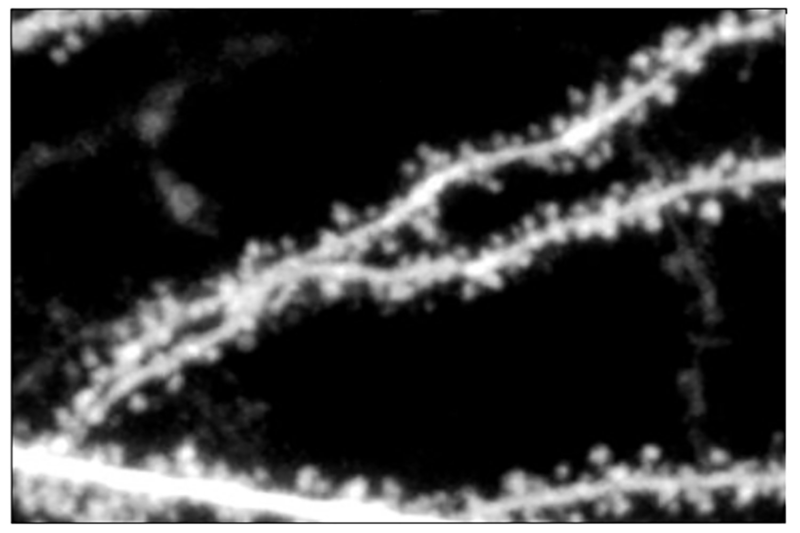

In the new study, Bear and Barnes’ team decided to use the non-ionic effect on spine shrinkage as a readout to dissect how NMDARs signal protein synthesis for synaptic plasticity in hippocampus neurons. They hypothesized that the dichotomy of ionic effects on synaptic function and non-ionic effects on spine structure might derive from the presence of two distinct components of NMDA receptors: “subunits” called GluN2A and GluN2B. To test that, they used genetic manipulations to knock out each of the subunits. When they did so, they found that knocking out “2A” or “2B” could eliminate LTD, but that only knocking out 2B affected spine size. Further experiments clarified that 2A and 2B are required for LTD, but that spine shrinkage solely depends on the 2B subunit.

The next task was to resolve how the 2B subunit signals spine shrinkage. A promising possibility was a part of the subunit called the “carboxyterminal domain,” or CTD. So, in a new experiment Bear and Barnes took advantage of a mouse that had been genetically engineered by researchers at the University of Edinburgh so that the 2A and 2B CTDs could be swapped with one another. A telling result was that when the 2B subunit lacked its proper CTD, the effect on spine structure disappeared. The result affirmed that the 2B subunit signals spine shrinkage via its CTD.

Indeed, when the scientists swapped in the 2B subunit CTD of NMDA receptor in fragile X model mice they found correction of not only the excessive bulk protein synthesis, but also altered synaptic plasticity, and increased electrical excitability that are hallmarks of the disease. To see if a treatment that targets NMDA receptors might be effective in fragile X, they tried an experimental drug called Glyx-13. This drug binds to the 2B subunit of NMDA receptors to augment signaling. The researchers found that this treatment can also normalize protein synthesis and reduced sound-induced seizures in the fragile X mice.